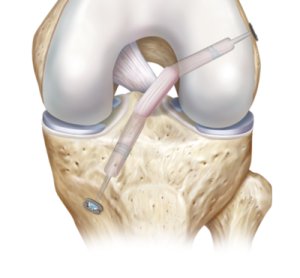

بازسازی ACL، با جایگزینی ACL پاره شده با گرفت جایگزین از خود بیمار (اتوگرفت) یا از اهداءکننده (آلوگرفت) صورت میپذیرد. این عمل جراحی؛ معمولا به صورت آرترسکوپی و با ایجاد تونلهایی در تیبیا و فمور صورت میپذیرد تا امکان قرارگیری گرفت جایگزین در محل آناتومیکال خویش مهیا شود. تکنیک جدید All-Inside این امکان را در اختیار جراح قرار میدهد تا بازسازی ACL را به صورت تمام آرتروسکوپی و با حداقل تهاجم به زانو به انجام برساند که خود باعث کاهش درد بعد از عمل بیمار خواهد گردید.

بازسازی ACL، با جایگزینی ACL پاره شده با گرفت جایگزین از خود بیمار (اتوگرفت) یا از اهداءکننده (آلوگرفت) صورت میپذیرد. این عمل جراحی؛ معمولا به صورت آرترسکوپی و با ایجاد تونلهایی در تیبیا و فمور صورت میپذیرد تا امکان قرارگیری گرفت جایگزین در محل آناتومیکال خویش مهیا شود. تکنیک جدید All-Inside این امکان را در اختیار جراح قرار میدهد تا بازسازی ACL را به صورت تمام آرتروسکوپی و با حداقل تهاجم به زانو به انجام برساند که خود باعث کاهش درد بعد از عمل بیمار خواهد گردید.